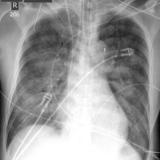

APE 1

Date: 11/05/2005

Views: 4196